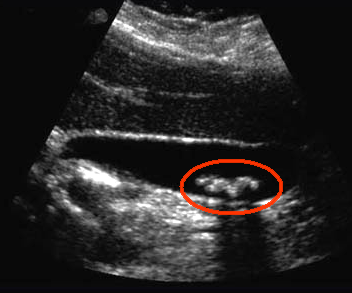

A

blood test showed that Ms GS had a high concentration of conjugated bilirubin

in her circulation, suggesting obstructive jaundice. She was sent for ultrasound

scan, which revealed the presence of gall stones, as shown on the right.